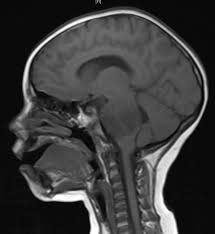

If your child is diagnosed with cancer, vcu massey cancer center is here to help. Cns tumors can develop anywhere in the brain or on the spinal cord. We provide a level of expertise found only at the top 4 percent of cancer centers across the country designated by the national cancer institute. This combination of mri images. The death rate was 0.7 per 100,000 children per year. The brain is part of the central nervous system (cns). If you have a topic of interest, let us know. Brain tumors and other nervous system tumors make up about 27 percent of childhood cancers. Rate of new cases and deaths per 100,000: The treatment, called a checkpoint inhibitor, has promise to help a. Sometimes just centimeters in size, these tumors present real treatment challenges because of their critical location in the brain. Brain and spinal cord tumors are the second most common cancers in children, making up about 26% of childhood cancers. Most brain tumors in children start in the lower parts of the brain, such as the cerebellum or brain stem.